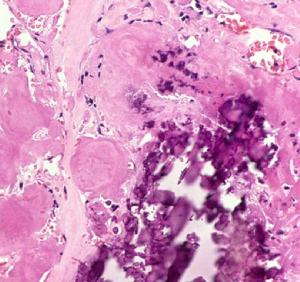

P物質

Substance P